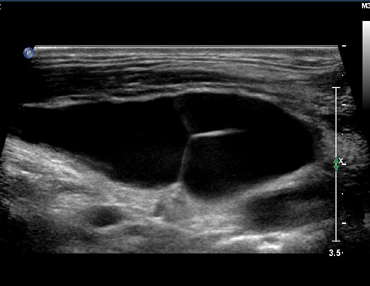

小腿横断面显示小隐静脉的“眼状”图

小隐静脉可不通过隐腘交界处直接移行为Giacomini静脉,上图所示为正常的SPJ结构与Giacomini静脉